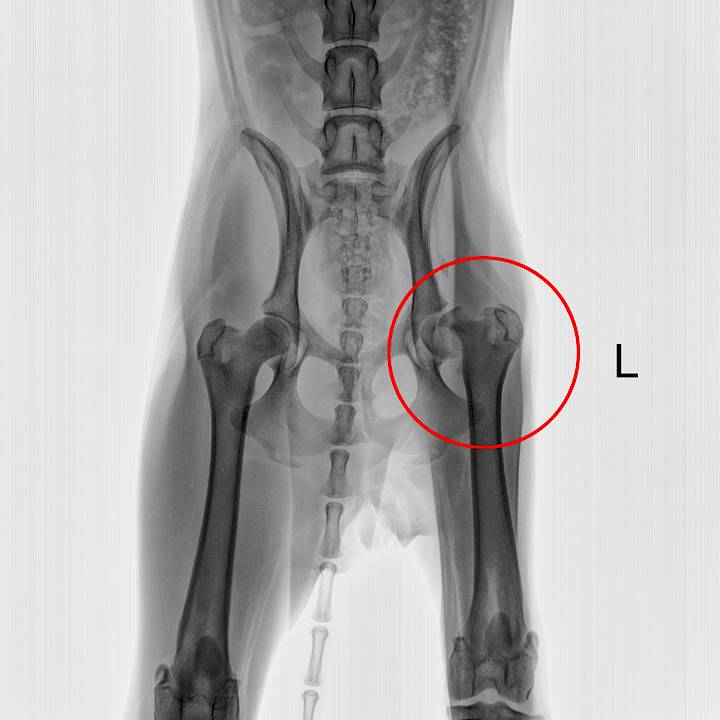

ซูกัสเป็นสุนัขที่แสนจะมีชีวิตชีวา เธอถูกรถชนจนได้รับบาดเจ็บ แต่โชคดีที่มีพลเมืองดีพบเห็นและนำเธอมารับการรักษาที่มูลนิธิของเรา เธอได้รับบาดเจ็บที่ขา ต้องเข้ารับการผ่าตัด และใช้ระยะเวลานานในการฟื้นฟูและกายภาพบำบัด หลังจากผ่าตัดได้ไม่นาน ซูกัสก็กลับมามีแรงอีกครั้งและพร้อมที่จะสนุกสนานกับชีวิตจนลืมไปว่าขาของเธอนั้นยังไม่หายดี